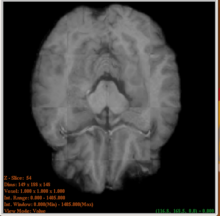

Segmentation of major tissue classes in for vervet subject

Subcortical Segmentation of Rhesus subject